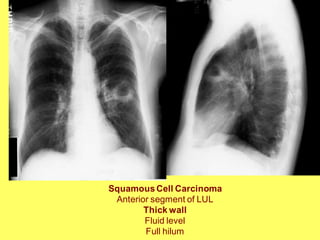

SquamousCell Carcinoma

Anterior segment of LUL

Thick wall

Fluid level

Full hilum

SquamousCell Carcinoma Lung

Irregular lumen

left hilar LN